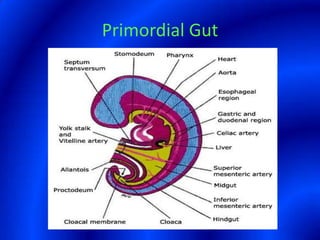

This document provides information about a barium swallow procedure. It begins with an introduction and overview of the embryology and anatomy of the pharynx and esophagus. It then describes the procedure itself, including preparation, technique, views obtained, and indications. Specific conditions that may be examined include pharyngeal and esophageal webs, foreign body impaction, scleroderma, dysphagia, mediastinal masses, and carcinoma. Diagrams are provided to illustrate normal anatomy and various pathological findings.